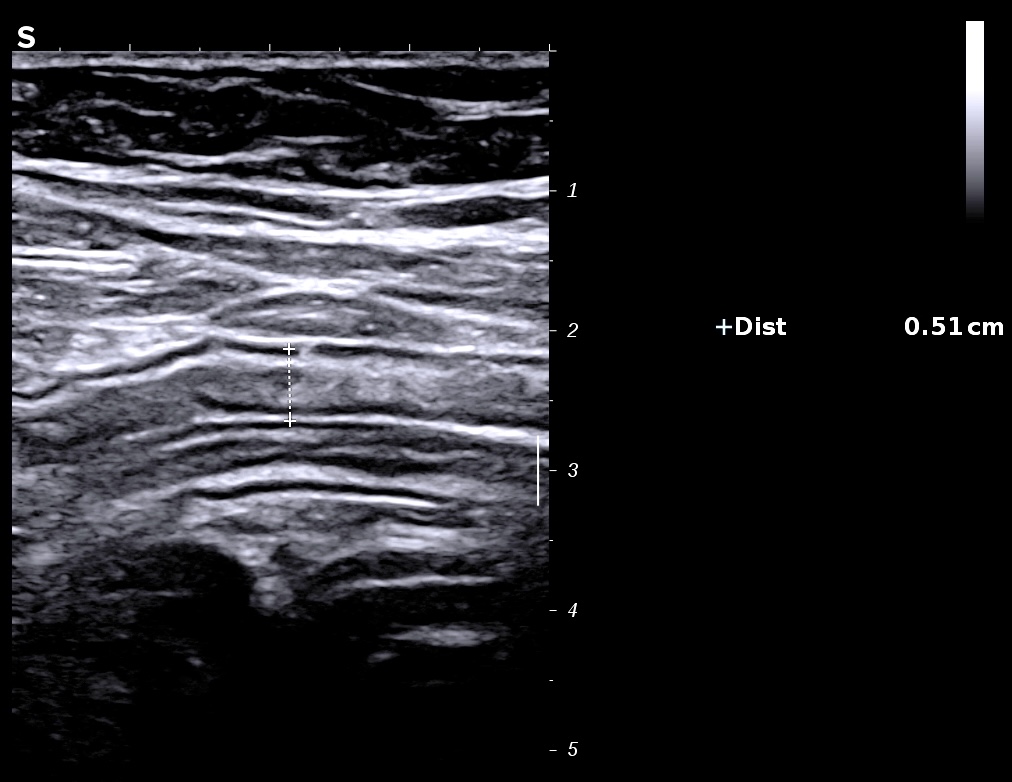

L'épaississement prédomine à la 3 ième couche hyperéchogène( > 1/3 de la paroi), il est continue, régulier, cironférentiel

La structure en couche est conservée

La graisse est peu infiltrée, l'activité doppler modérée.

Exemple de paroi de 5 mm avec début de la disparition de la structure en couches (le contraste entre la muqueuse et la sous muqueuse est moins visible)